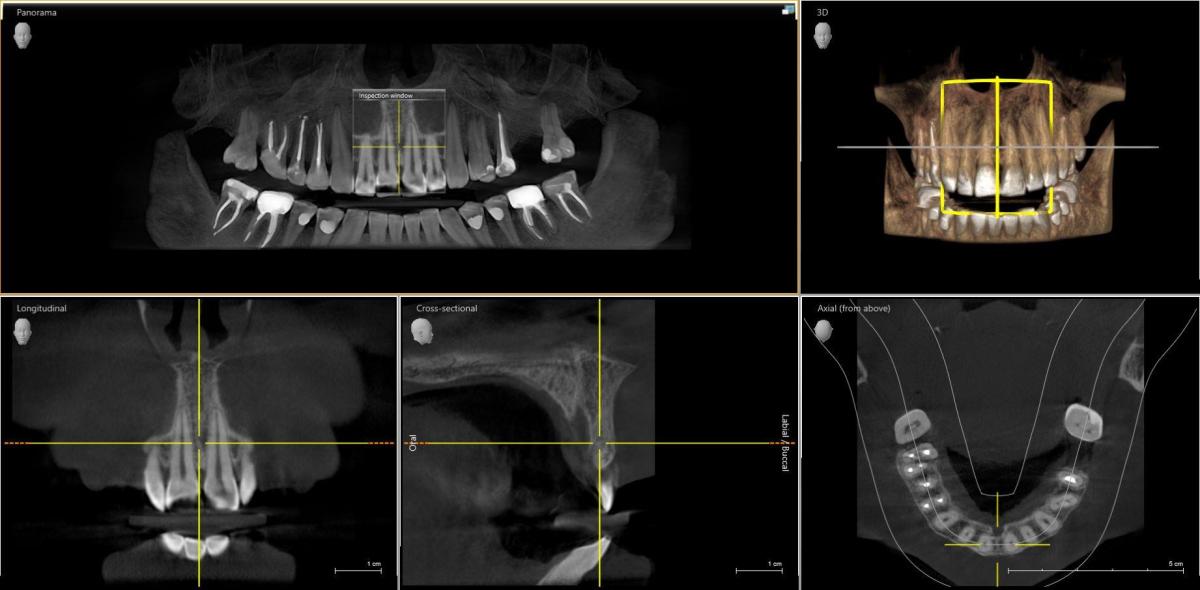

Юрий Жигурт, теперь запуталась, их тут кт называют, есть 3 д снимок, сделала, завтра будет. Он подойдет?

Мария Борисова, добрый день, Мария. Вот еще картинка. Если вам не сложно, посмотрите, пожалуйста. У меня гацморит и фронтит левосторонний постоянно

не информативные срезы. Вы в Москве? Надо центральное окошко сдвинуть влево

Не могу открыть файл... поэтому не сделаю другую картинку, увы.